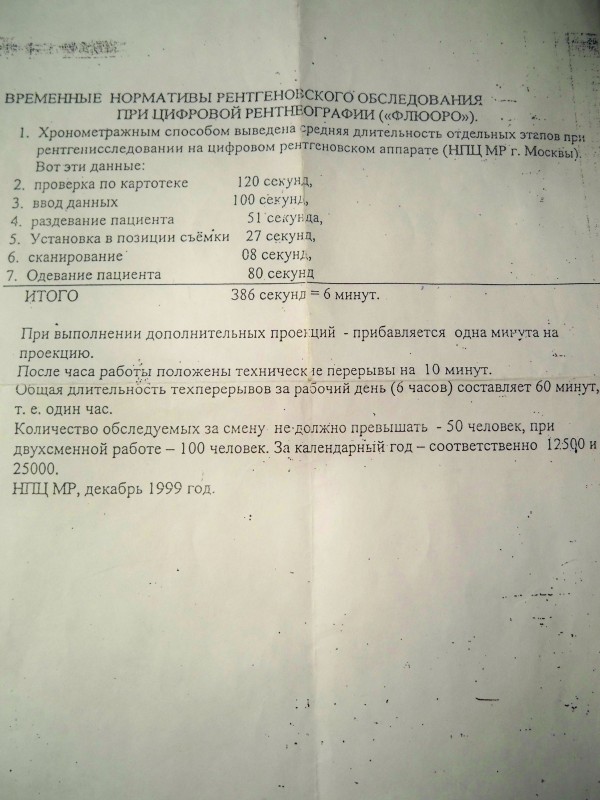

Изучение дозы излучения при рентгеновских исследованиях: визуализация